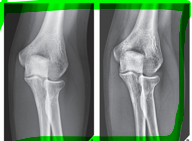

What is the centre point for this radiograph? - patient is in right lateral recumbency for a medio-lateral view of the stifle joint

The stifle joint

What are the collimation borders for this radiograph? - patient is in right lateral recumbency for a medio-lateral view of the stifle joint

Cranial and caudal skin edges, mid-shaft femur and mid-shaft tibia and fibula

What does this radiograph show?

Cranio-caudal stifle joint

What is the centre point of this radiograph?

Stifle joint

What are the collimation borders for this radiograph?

Distal femur, proximal tibia and fibula, lateral skin edges

Is there anything missing on this radiograph (radiograph created using a computed radiography system) ?

Right/left marker

What anatomical structure is the red arrow pointing to?

Patella